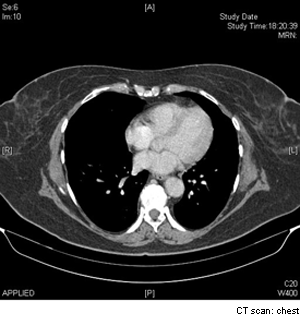

What diagnostic technique does this image depict?

CT scan